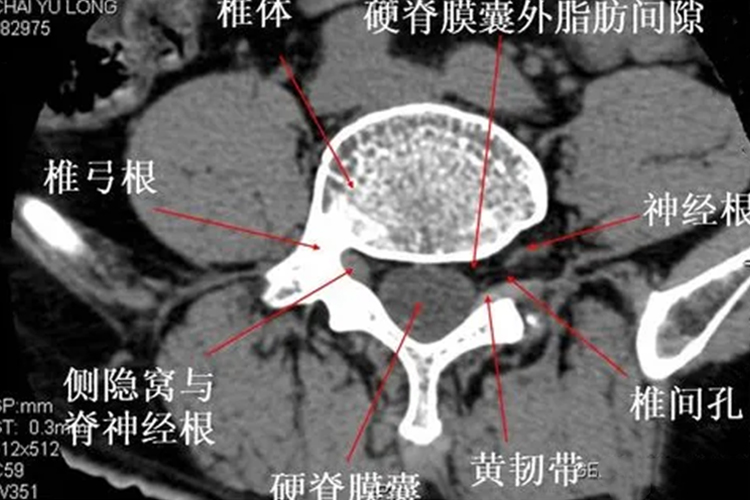

腰椎侧隐窝在侧椎管处,是椎管两侧的延伸部,其外界为椎弓根内壁,后方是上关节突前壁、黄韧带外侧部及相应椎板上缘,前方是椎体后缘的外侧部分及相应的椎间盘,内侧为开放区,与硬膜及硬膜外脂肪、血管丛相邻。侧隐窝内有从硬膜囊内穿出的神经根通过,并向外进入椎间孔。